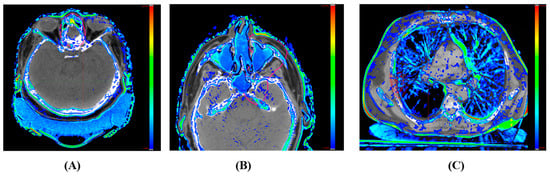

For IC sCT, certain situations display substantial HU discrepancies between the vCT and the IC sCT, especially in low-density regions. The resulting synthetic CT often has an HU approximately 100–200 units higher than the HU value of vCT in areas such as the head cushion, nasal cavity air region, and vacuum bag region, as illustrated in Figure 9A–C. It is advised to rectify such HU discrepancies before advancing with calculations on the synthetic CT images.

Figure 9. Differences in Hounsfield unit (HU) values between the image-corrected (IC) synthetic CT and the reference verification CT. The color bar indicates an HU discrepancy scale, spanning from 100 to 1000 HU. (A) Immobilization head cushion area; (B) nasal sinus region; (C) lung tissue and Vac-Lok TM region.